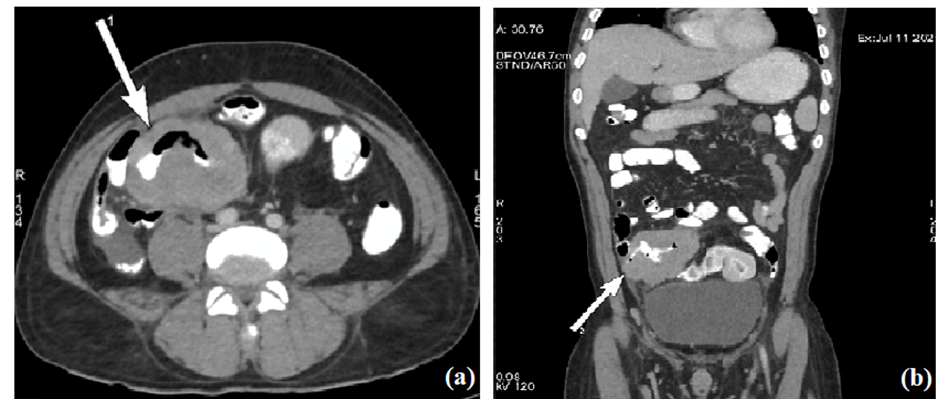

Histopathological examination revealed sheets of large atypical lymphoid cells with vesicular nuclei and prominent nucleoli, consistent with diffuse large B-cell lymphoma (DLBCL). Immunohistochemistry showed:

• CD20 positivity

• High Ki67 proliferation index (95%)

• Dim MUM1 reactivity

These findings confirmed a diagnosis of DLBCL, non-germinal center type.

The post-surgery histopathology report indicated non-Hodgkin's lymphoma, while microscopic examination showed large atypical lymphoid cells, typical of diffuse large B cell lymphoma (DLBCL). Immunohistochemistry confirmed the lymphoma's type and grade, with diffuse reactivity for CD20 and a high Ki67 proliferation index, suggesting non-germinal center type of DLBCL. The lymphoma's non-germinal center type was further confirmed through IHC.

Fig. 3. High power histopatological images showing monotonous infiltrate of large atypical lymphoid cells with scant cytoplasm and vesicular nuclei suggestive DLBCL.

Fig. 4a. IHC images showing diffuse reactivity for CD20 with (b) high Ki67 proliferation index of 95%. (c) Also dim nuclear reactivity for transcription factor MUM1, suggestive of DLBCL non-germinal centre type.

Histopathology combined with immunohistochemistry (IHC) confirmed a high-grade DLBCL, non-germinal center type, characterized by CD20 positivity and a high Ki-67 proliferation index, indicating aggressive biological behavior. This subtype is known for a less favorable prognosis compared to germinal center types but responds well to R-CHOP (rituximab, cyclophosphamide, doxorubicin, vincristine, and prednisone), the current standard of care for DLBCL.